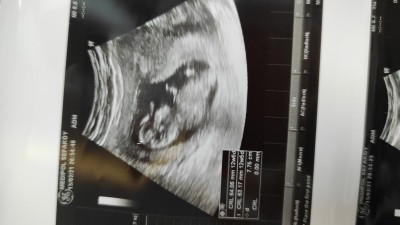

14 haftalık hamileyim ultrason da cinsiyet belli mi sizce

Gebelik haftası 14

Bana erkek gibi geldi canım doktorun tahminde bulundu mu

Yok hayır bir ay sonra cevap veririm dedi şuan kesin bişey diyemem dedi

Pozisyon  uygun  değil  ki

Görünmüyor demi